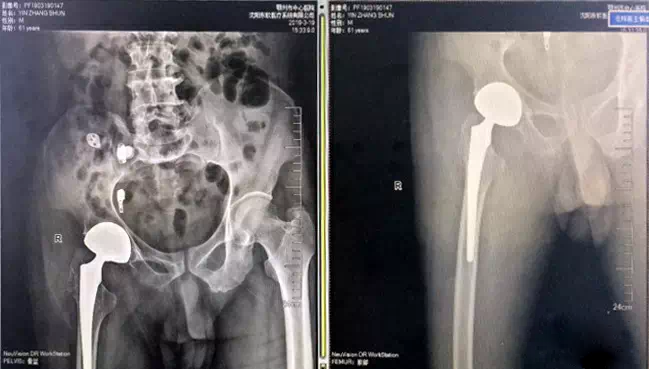

(术后X光片)

据了解,仿生双动全髋关节仿照人体原有髋关节的生理形状设计制造,适用于比传统髋关节置换更高要求的患者,比如活动度大,配合度欠佳,易脱位的患者。与传统的髋关节材料相比,它具有超高的稳定性、超低的磨损率、超大的关节运动幅度,实现髋臼“零”脱位率的可能,为患者缩短了住院时间,提供更高的生活质量。